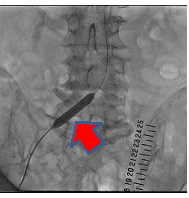

経皮的腎動脈形成術の一例

- 【1】術前

-

- 【2】ステント留置

- 【3】術後